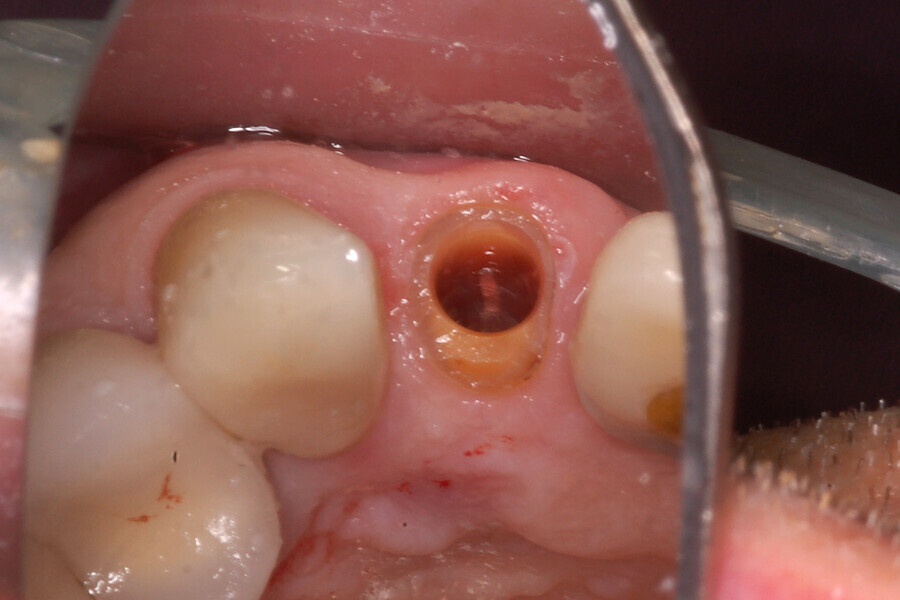

Fig. 12b: The occlusal view illustrated the cervical tissue volume and contours.

Fig. 26c: The abutment in place.

Fig. 26d: The soft-tissue contours were excellent; no sutures were required for the transitional restoration.